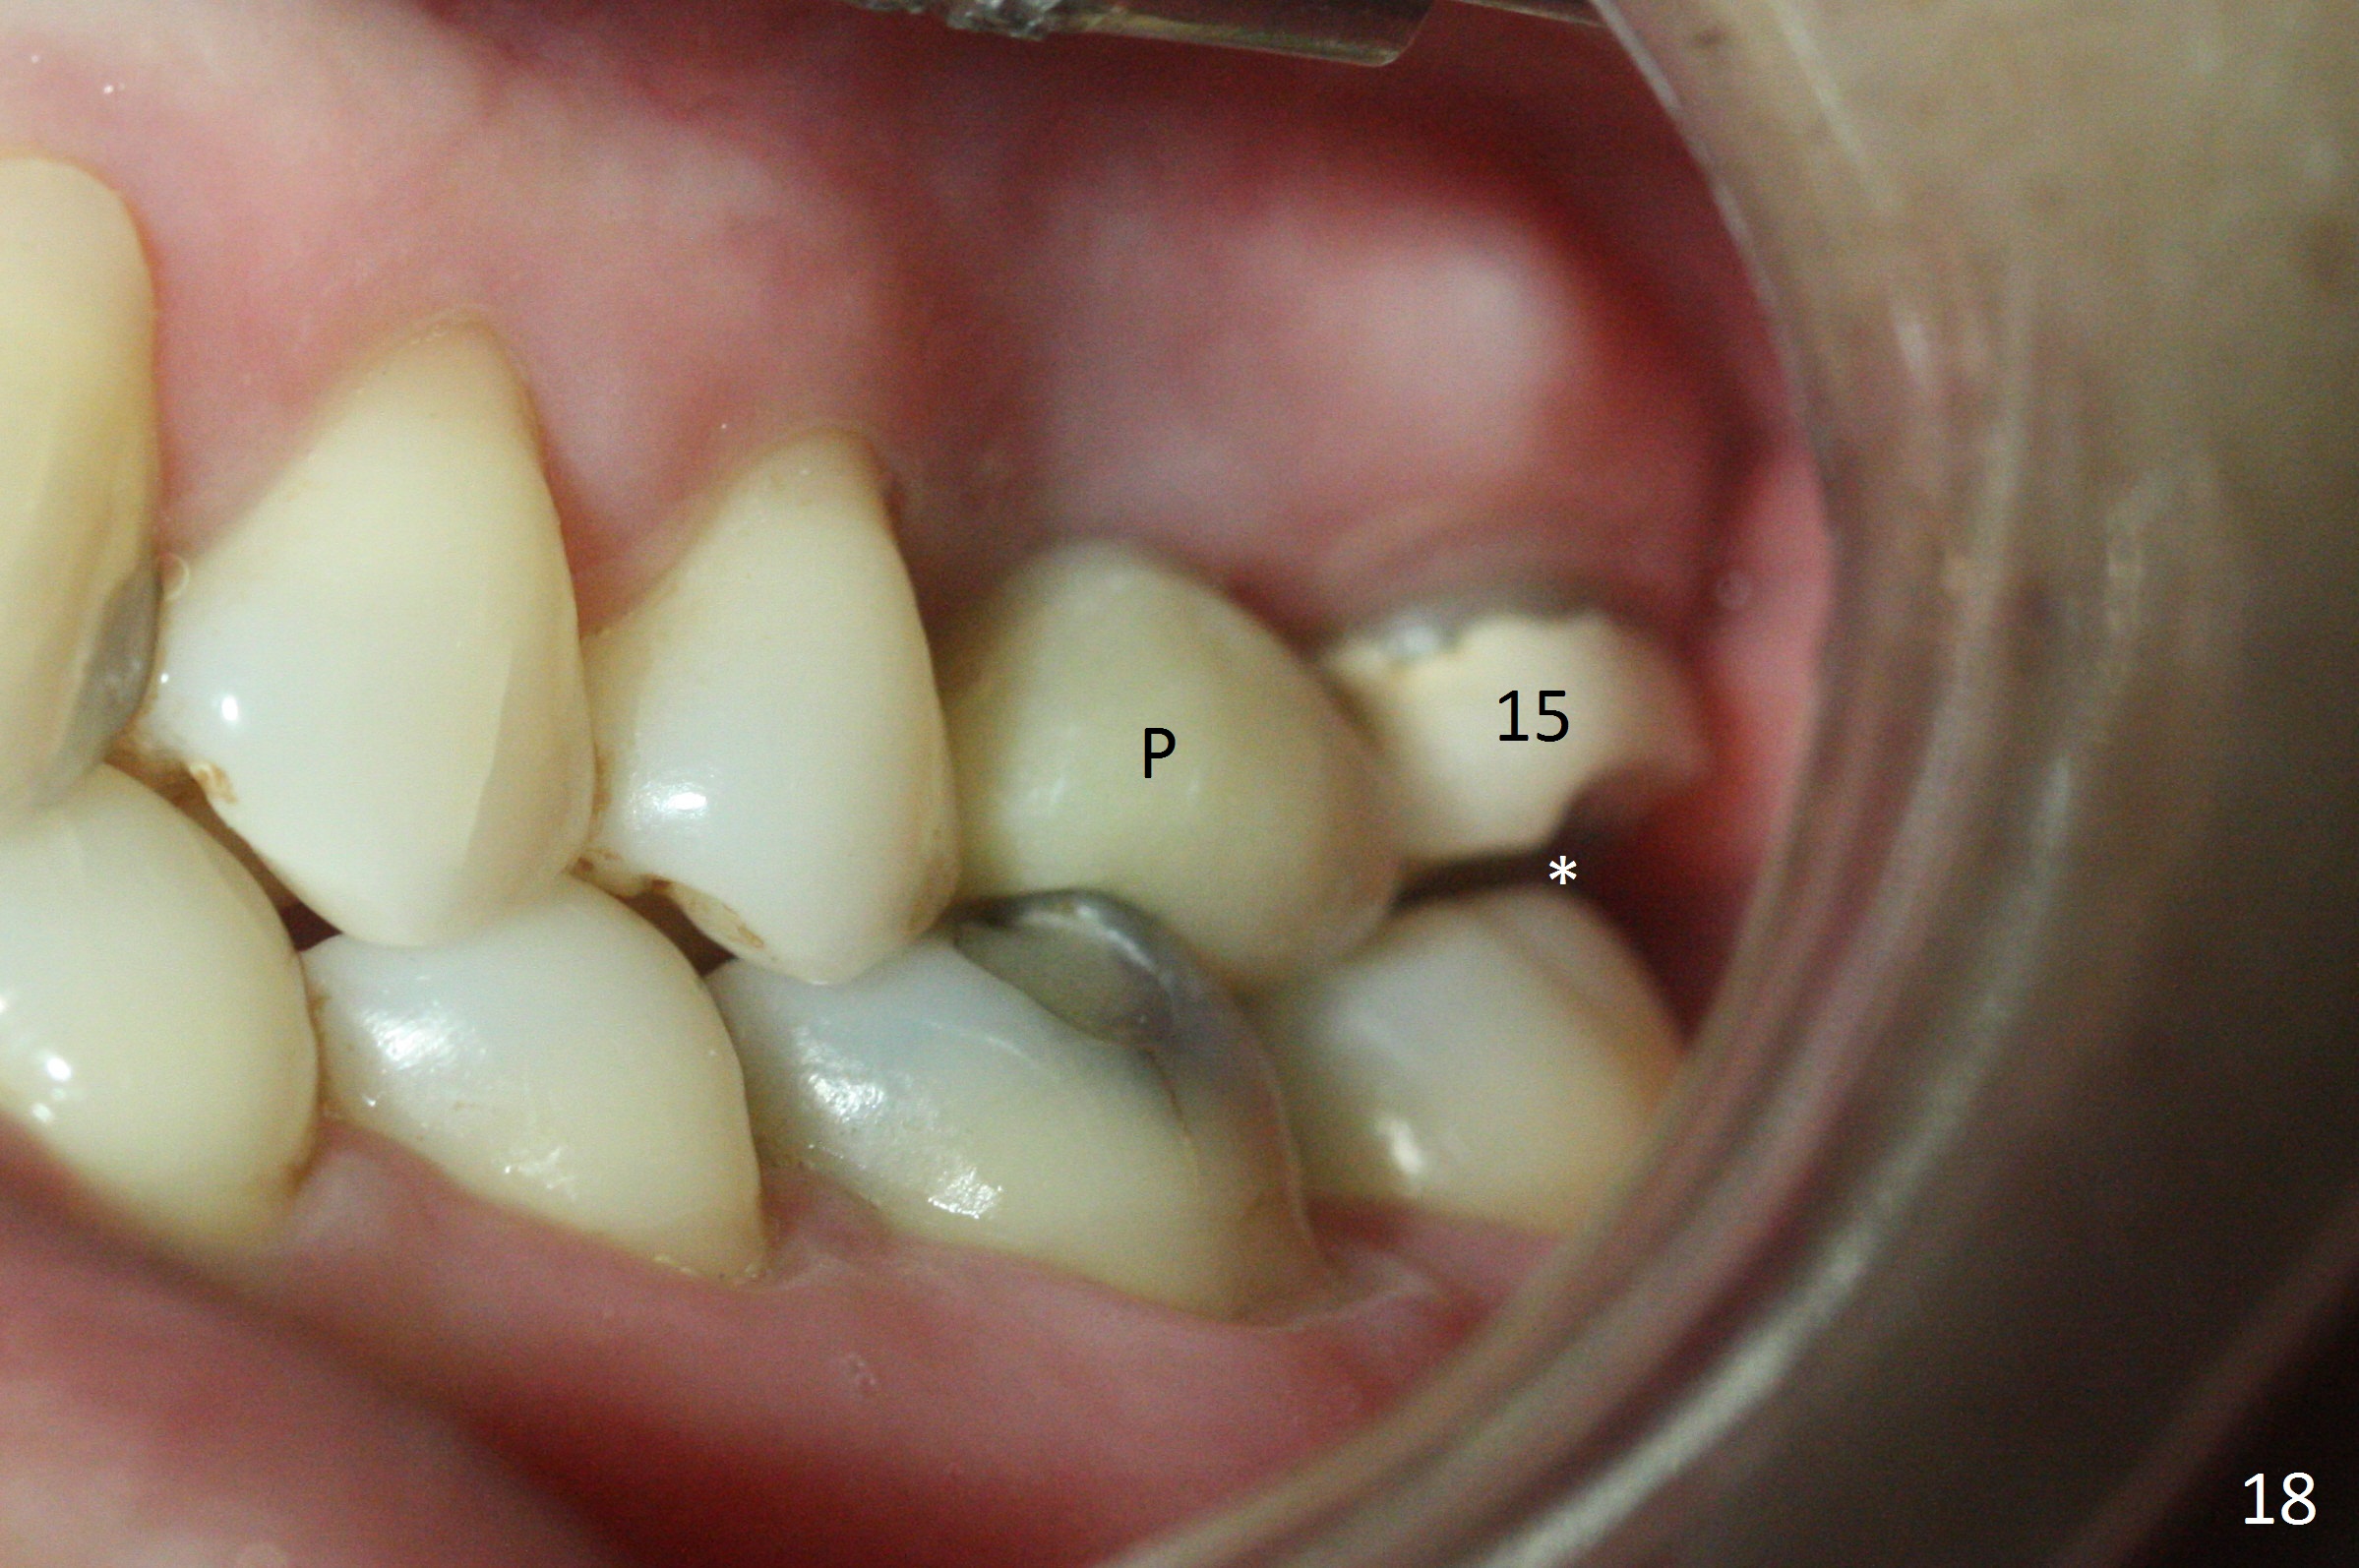

The implant is stable 8 months postop (Fig.15). When a 6x4(3) mm abutment is placed 8.5 months postop, it is distal (Fig.16). The mesiodistal width is 1-2 mm shorter than that at #3, which suggests the mesial shift of the tooth #15. A provisional is fabricated at #14 (Fig.17 P) with supra-occlusion so that there is clearance between the tooth #15 and the opposing one (Fig.18 *). With a separator placed between #14 and 15 (Fig.19), the latter is free to be distalized. Bone volume and density seem to increase 4.5 and 10.5 months post cementation (Fig.20,21, as compared to Fig.15), although the buccal plate remains as concave as shown in Fig.18. One year 5 months post cementation, the patient complains of bad smell from the implant when water pik is being used. It appears that the 1st 2-3 threads are exposed (Fig.22), although the surrounding gingiva remains uninfected. Bone graft is recommended. The site heals without bad smell 7 months post bone graft (2 years 4 months post cementation, Fig.23). The 1st implant thread is found exposed buccal on uncover (regraft?). A small healing abutment is placed because the implant is placed distal (Fig.24). An angled abutment should be tried and #15 crown will be redone. Impression will be taken when the gingiva heals around the provisional crowns.